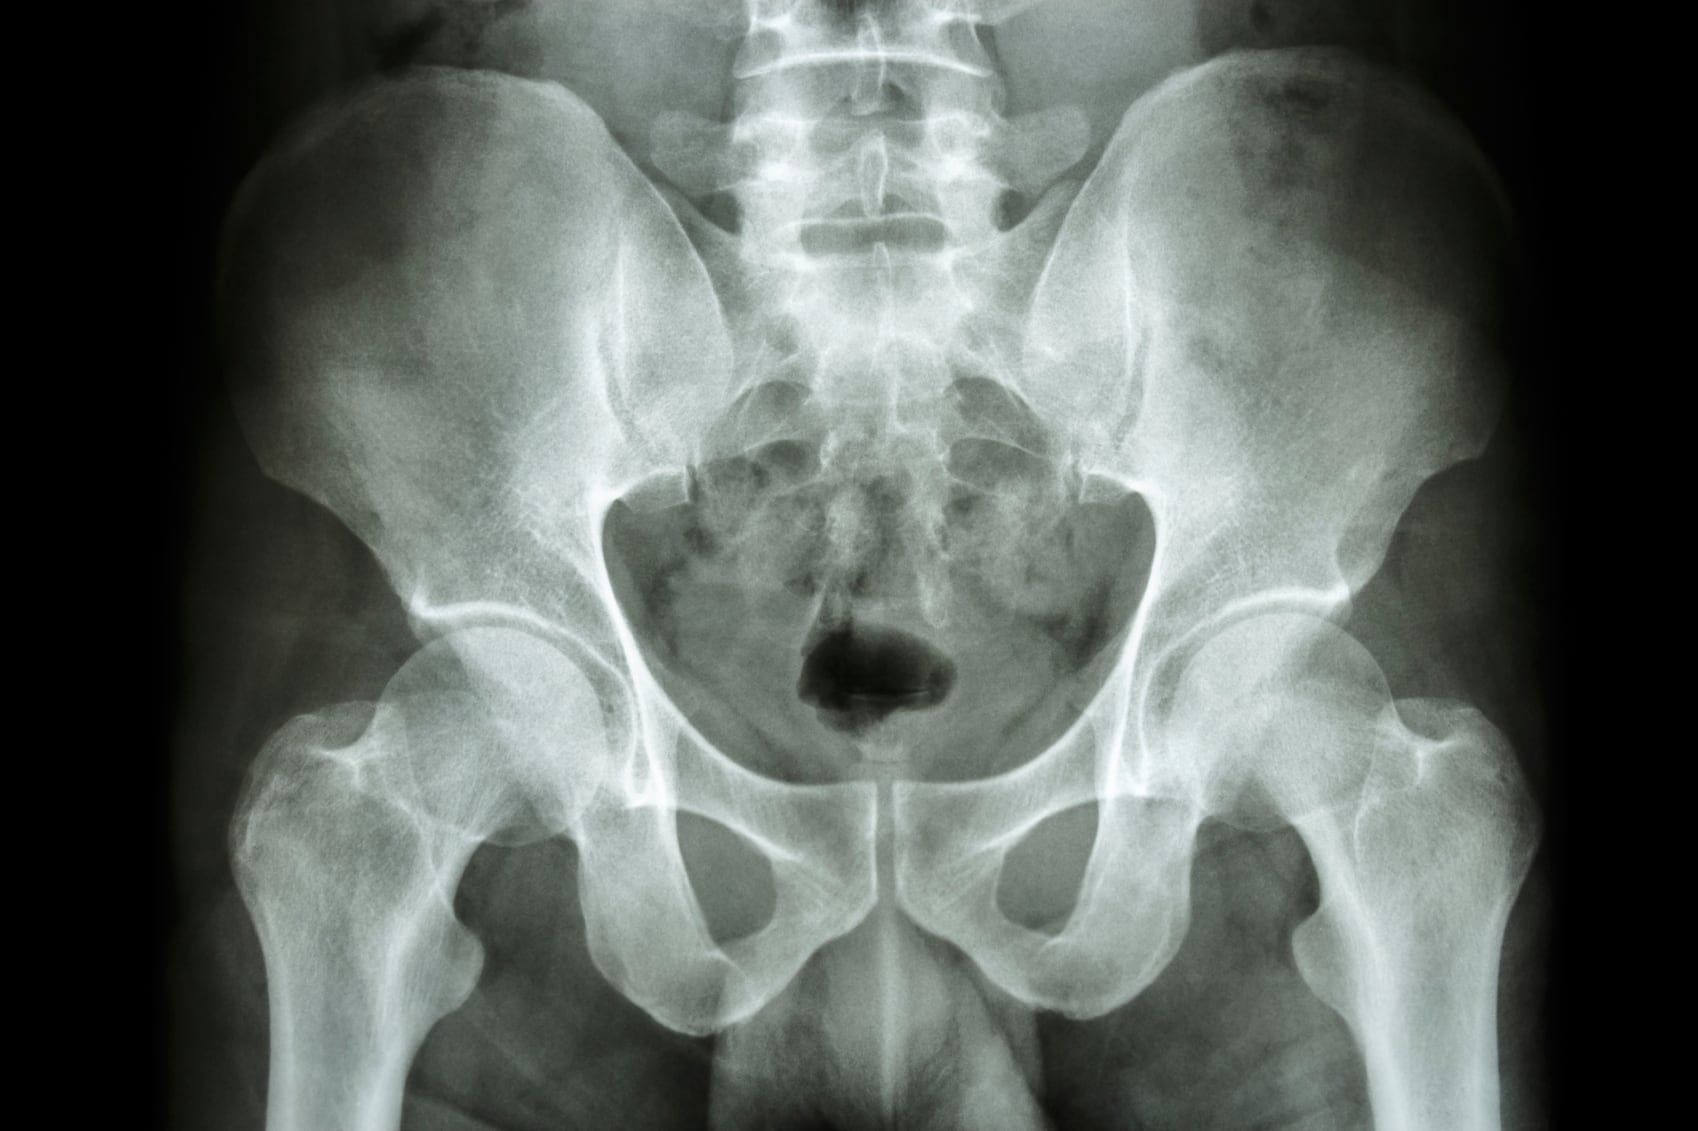

Calcium intake for women, especially as they approach and undergo menopause, is of special concern because of their greater risk for developing osteoporosis, one of the conditions that can have a huge impact on quality of life for older women. The bones act as a calcium bank, so to speak, with calcium being released into the bloodstream from the bones as needed for basic functions. Bone density can drop when the pace of calcium outflow exceeds the amount of calcium needed to keep up with ongoing process of bone formation known as bone remodeling. Vitamin D plays an important role in this process, and there is some evidence to indicate that an adequate level of vitamin K2 is also important in modulating calcium mobility.

- High calcium intake alone—either from food or supplements—doesn't prevent hip fracture.